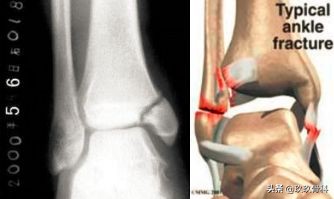

踝的骨折▲▲▲

鉴别诊断

- 内外踝骨折